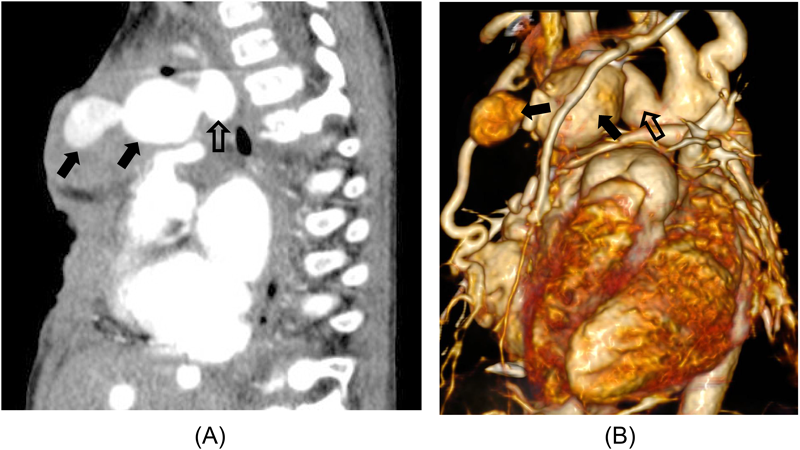

感染性腕頭動脈瘤に対してカバードステント留置術を行った乳児例An Infantile Case of Covered Stent Implantation for Infectious Aneurysms of the Brachiocephalic Artery